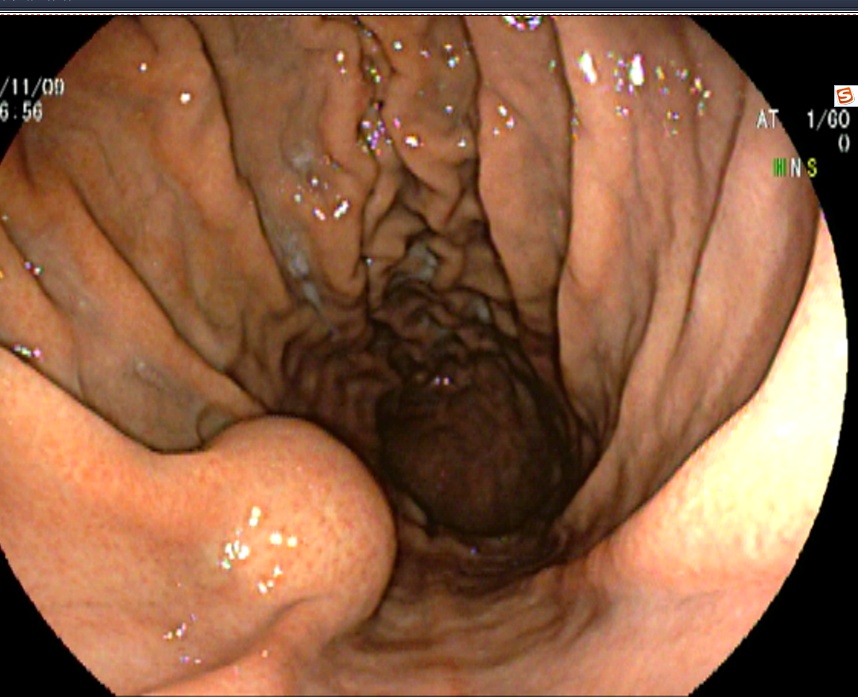

病房收治一名女性患者,68岁

患者主诉:阵发性上腹痛半月余

门诊行无痛胃镜,慢性浅表——萎缩性胃炎,胃石形成,建议内镜下治疗。

治疗效果

兰索拉唑抑酸1周(30mg bid)和碳酸氢钠片口服1周(600mg tid),补液支持。

一周后镜下复查,胃石消除。